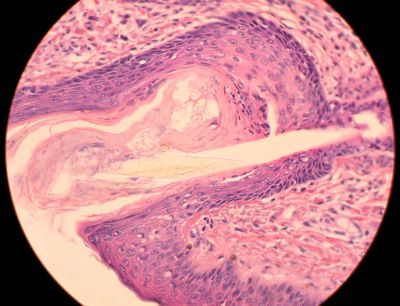

External ear, monkey - histology slide

This is a histology slide of the external ear of a monkey.

Histology slide courtesy of Florida State University.